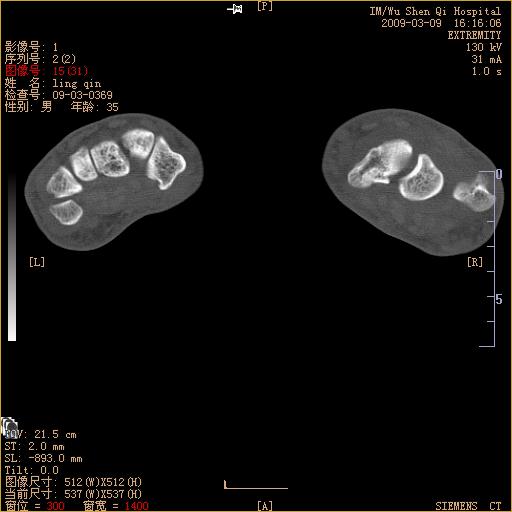

标题: CT18570:右手外伤10余天 [打印本页]

标题: CT18570:右手外伤10余天

腕部有骨折、脱位,骨科面对ct片如何采取措施?三维一下。

舟状骨骨折。

左侧舟骨及桡骨茎突骨折,第一掌骨基底部好像也有骨折,建议上传平片